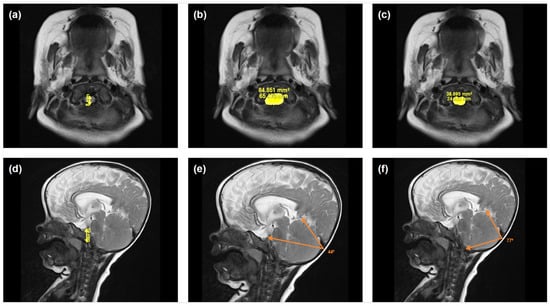

Illustrative examples of key anatomical structures on MRI scans from children with achondroplasia are shown in Figure 1 and Figure 2. Of the 12 parameters measured and analyzed from the MRI scans, 10 showed significant differences between the achondroplasia and reference groups (Figure 3; Table S1). The diameter (mean 10.0 mm vs. 16.1 mm; p < 0.001) and area (mean 109.0 mm2 vs. 160.8 mm2; p = 0.005) of the foramen magnum were significantly smaller in children with achondroplasia compared with the reference group. Furthermore, the myelon area was significantly smaller (mean 40.6 mm2 vs. 47.7 mm2; p = 0.004) and the clivus significantly shorter (mean 23.5 mm vs. 30.3 mm; p < 0.001) in children with achondroplasia. The tentorium angle was significantly steeper in children with achondroplasia (mean 47.6 degrees vs. 38.1 degrees; p < 0.001) and was accompanied by a larger volume of “overhang” of the brainstem from the posterior cranial fossa (mean 4542.5 mm3 vs. 2614.4 mm3; p < 0.001). A significantly smaller volume of the fourth ventricle (mean 749.9 mm3 vs. 1056.2 mm3; p = 0.029) and corresponding significantly larger volume of the supratentorial ventricular system (mean 42,062.3 mm3 vs. 13,389.2 mm3; p < 0.001) was also observed in patients with achondroplasia. No significant differences between the achondroplasia and reference groups were observed in posterior fossa or cerebellum volume.

Figure 1. Illustrative examples of selected anatomical structures measured from magnetic resonance imaging scans from a child with achondroplasia. Shown are images used to calculate the following parameters: (a) foramen magnum diameter, (b) foramen magnum area, (c) myelon area, (d) clivus length, (e) tentorium angle, and (f) occipital angle.